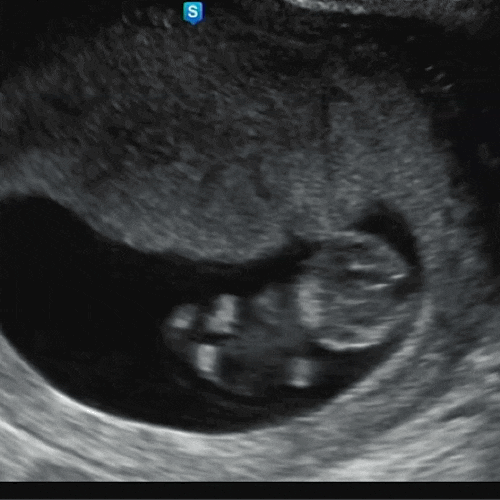

첫번째 임신 기록 (5주~17주)

2024년 1월 1일. 새해 선물같이 우리에게 찾아와 준 아기. 부모가 되고 싶다는 마음을 먹은 후 선물처럼 바...

18주차 임산부가 되었다. 똥배 같았던 내 배가... 뭔가 더 큼직해졌다. 20주부터 나와야 한다고 하는데, 뭔...